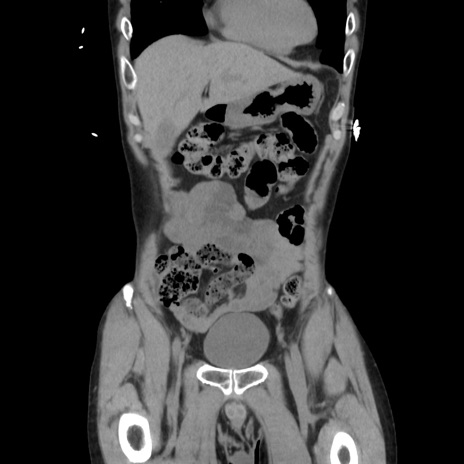

症例37(冠状断像)

【症例】40歳代 男性

【主訴】腹痛

【現病歴】4時間ほど前に電車に乗車中に臍部上より腹痛出現。徐々に増悪し起立困難となり、救急外来受診。生ものは数日食べていない。今朝お雑煮を食べた。

【身体所見】BT 36.8℃、BP 117/84mmHg、HR 91/min、SpO2 97%、苦悶様、腹部:臍上部広範囲圧痛あり、反跳痛±

【データ】WBC 8100、CRP 0.03